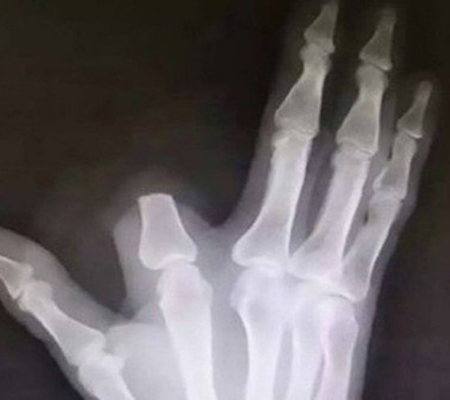

Um agricultor chinês, de 60 anos, tomou uma medida drástica após ser picado por uma cobra. Desesperado, Zhang decepou parte do dedo ferido a fim de evitar que o veneno se espalhasse. O caso aconteceu recentemente na zona rural de Shangyu (província de Zhejiang), de acordo com o "South China Morning Post". As informações são do Extra.

Ao chegar a um hospital em Hangzhou, cidade localizada a 80 quilômetros da residência do chinês, ele descobriu que a serpente não era exatamente a que ele identificara.

Foto: Reprodução/WeiboMais do que isso: o paciente não apresentava nenhum dos sintomas daqueles picados por cobras venenosas de alto risco: problemas respiratórios, forte dor de cabeça e sangramento. Na verdade, o veneno da víbora que picara o agricultor é muito fraco, com efeito mínimo sobre humanos. Zhang cortou o pedaço do indicador à toa. E ele não pôde ser reimplantado.

"Não era necessário cortar. Aquela cobra não é tão tóxica", declarou o médico Yuan Chengda, que atendeu Zhang.